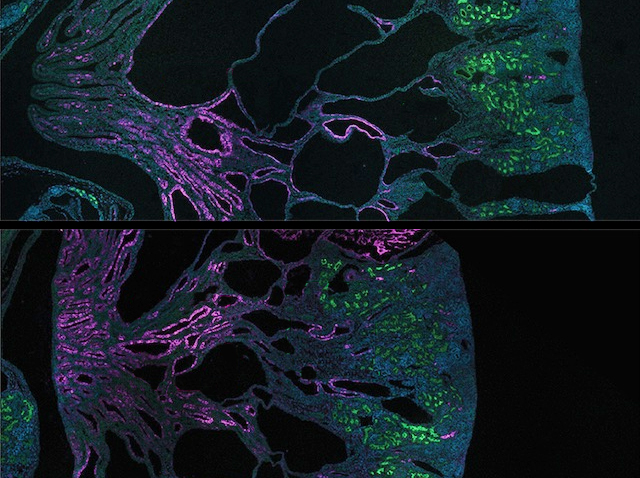

Les característiques que definixen les cèl·lules mare són la seua capacitat de convertir-se en diversos tipus cel·lulars i la seua habilitat per a autorenovar-se. Aquesta capacitat d’autorenovació garantix el manteniment de les reserves de cèl·lules mare en el cos i, si els científics saben aprofitar-la bé, també al laboratori. Quan es mantenen cultius de cèl·lules mare al laboratori, els investigadors solen utilitzar diferents combinacions de factors específics per a cada tipus de cèl·lula mare. No obstant això, investigacions recents han identificat un punt de control comú (la quinasa reguladora GSK3), que, quan s’inhibix, manté la capacitat d’autorenovació en diversos tipus de cèl·lules mare i en diferents espècies. De fet, la inhibició de GSK3 ha permés cultivar conjuntament epiblasts de ratolí i cèl·lules mare embrionàries, com es mostra a la imatge (en verd i roig), mantenint alhora les seues identitats pròpies, cosa que fins ara era impossible. A més de millorar les tècniques de cultiu de cèl·lules mare, el descobriment d’aquest punt de control comú podria tindre aplicacions clíniques per a millorar la salut i la regeneració de teixits envellits.

Imatge de Duo Wang/Ying Lab/USC Stem Cell. Publicació de Duo Wang i Xiukun Wang, i col·laboradors/es

Eli and Edythe Broad Center for Regenerative Medicine and Stem Cell Research at USC, Keck School of Medicine, USC, Los Angeles, CA; Epigenetics and RNA Biology Laboratory, National Institute of Environmental Health Sciences, Durham, NC, EUA

Publicat en Cell Research, abril de 2026